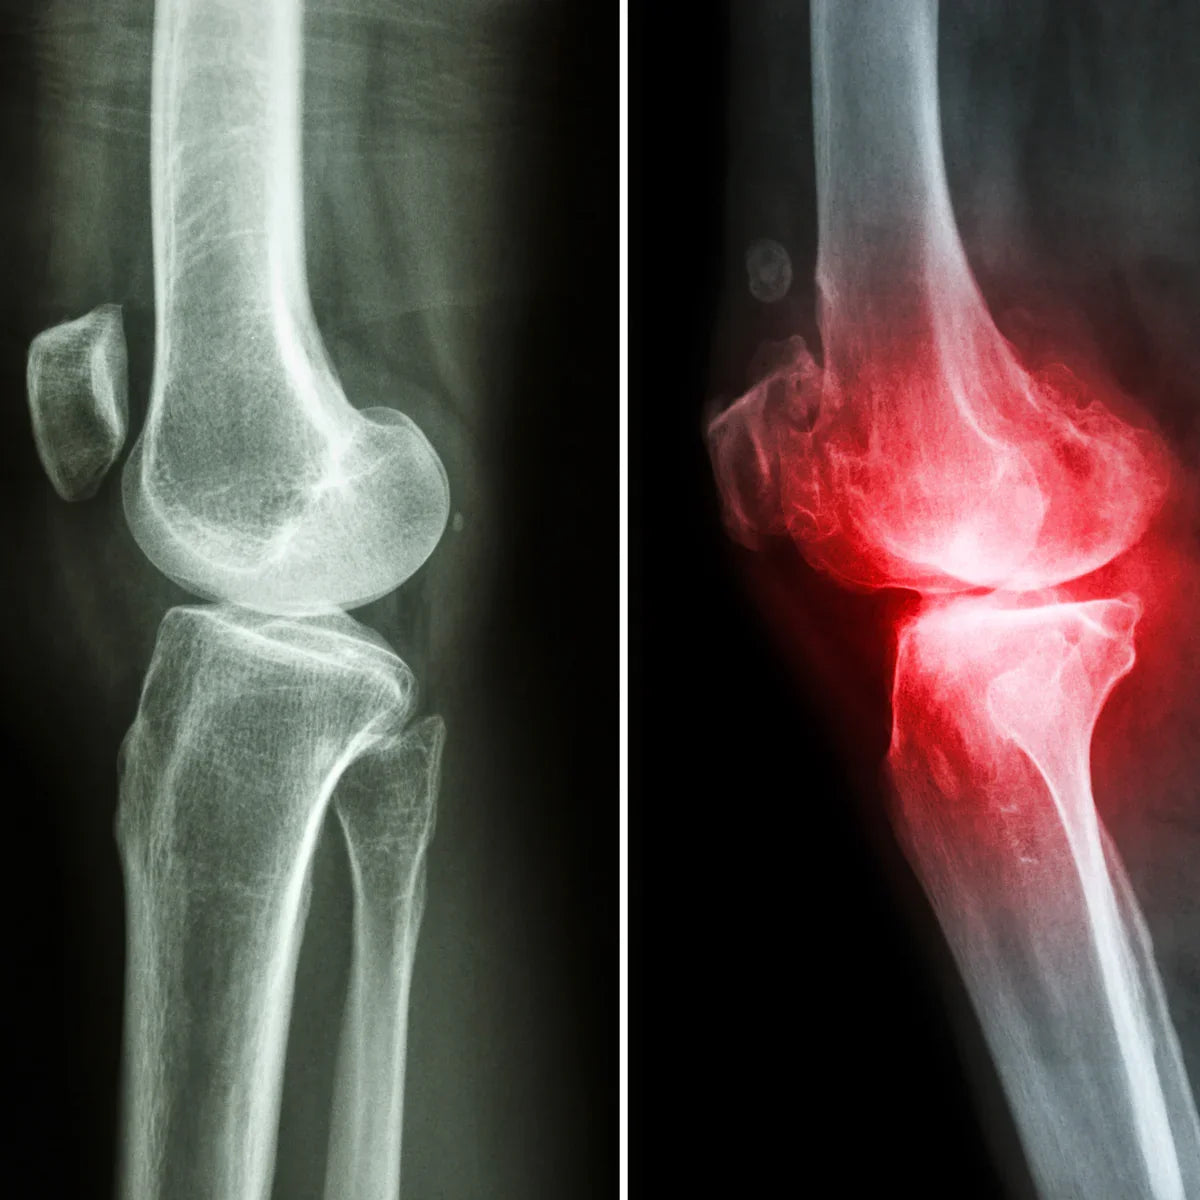

Arthro4 je kompleks za smanjenje upale zglobova i jačanje hrskavice s bioaktivnim biljnim sastojcima. Njegova glavna komponenta je novozelandska dagnja zelenih usana i uključuje koncentrate aktivnih sastojaka 3 najjače prirodne biljke za potporu zglobovima i hrskavici: đavolja kandža, kurkuma i boswellia ekstrakt.

| ✓ Osteoartritis |

| ✓ Reumatoidni artritis |

| ✓ Bol u koljenu |

Trošenje hrskavice uzrokovano je degeneracijom hrskavice koja štiti zglobove. Istraživanja sugeriraju da boswellia pomaže spriječiti ovo oštećenje u zglobnim tkivima i hrskavici. [04.]

- Prikladno za liječenje upale kostiju i zglobova, osteoartritisa i reumatoidnog artritisa zbog svojih protuupalnih učinaka.

- Smanjuje oticanje i ublažava bol kod pacijenata s upalom zglobova.